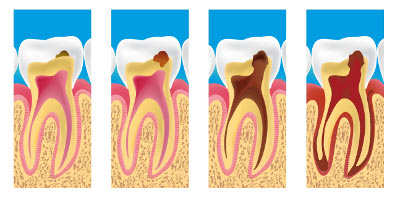

Les premiers signes peuvent apparaître une fois que la carie a atteint la dentine. Mais parfois la douleur ne survient que très tardivement. C'est pourquoi il est vivement conseillé de ne pas attendre d'avoir mal pour consulter un praticien. Douleurs au froid et au sucré signent le plus souvent une carie active ou une dénudation du collet dentaire, qu'il est urgent de faire traiter. Douleurs au chaud ou à la pression signent généralement une reprise de carie sous une obturation qui a évolué à bas bruit et a provoqué la nécrose de la dent concernée. Dommages visibles : initialement tache blanche (pas toujours très visible). Une tache marron (plus ou moins foncé) signe une carie ancienne, reminéralisée, qui n'est plus active. Lorsqu'on remarque un trou dans la dent, la carie est déjà avancée ; la dent risque de devoir être dévitalisée.

Dévitalisation

Lorsque la carie a atteint un stade avancé, le dentiste doit dévitaliser la dent, puis obturer les canaux dans lesquels se trouvait la pulpe afin de prévenir une infection bactérienne. Le dentiste réalise le traitement radiculaire ou dévitalisation d'une dent lorsque celle-ci ne peut plus être gardée vivante, soit parce qu'elle est déjà nécrosée, soit parce qu'elle risque de le devenir.